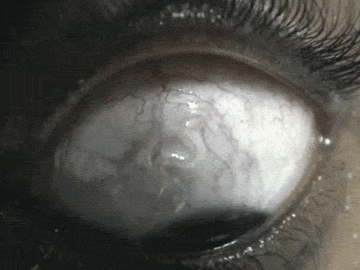

▼6.罗阿罗阿丝虫(Loa loa)。

▼牠们首先会寄生在斑虻上,斑虻吸食人体血液时,牠们就会顺势进入人体。这种寄生虫超爱人类的眼球,蜕皮2次后就会跑到眼球上,等到眼球被感染坏死,牠们就会跑到脑部。